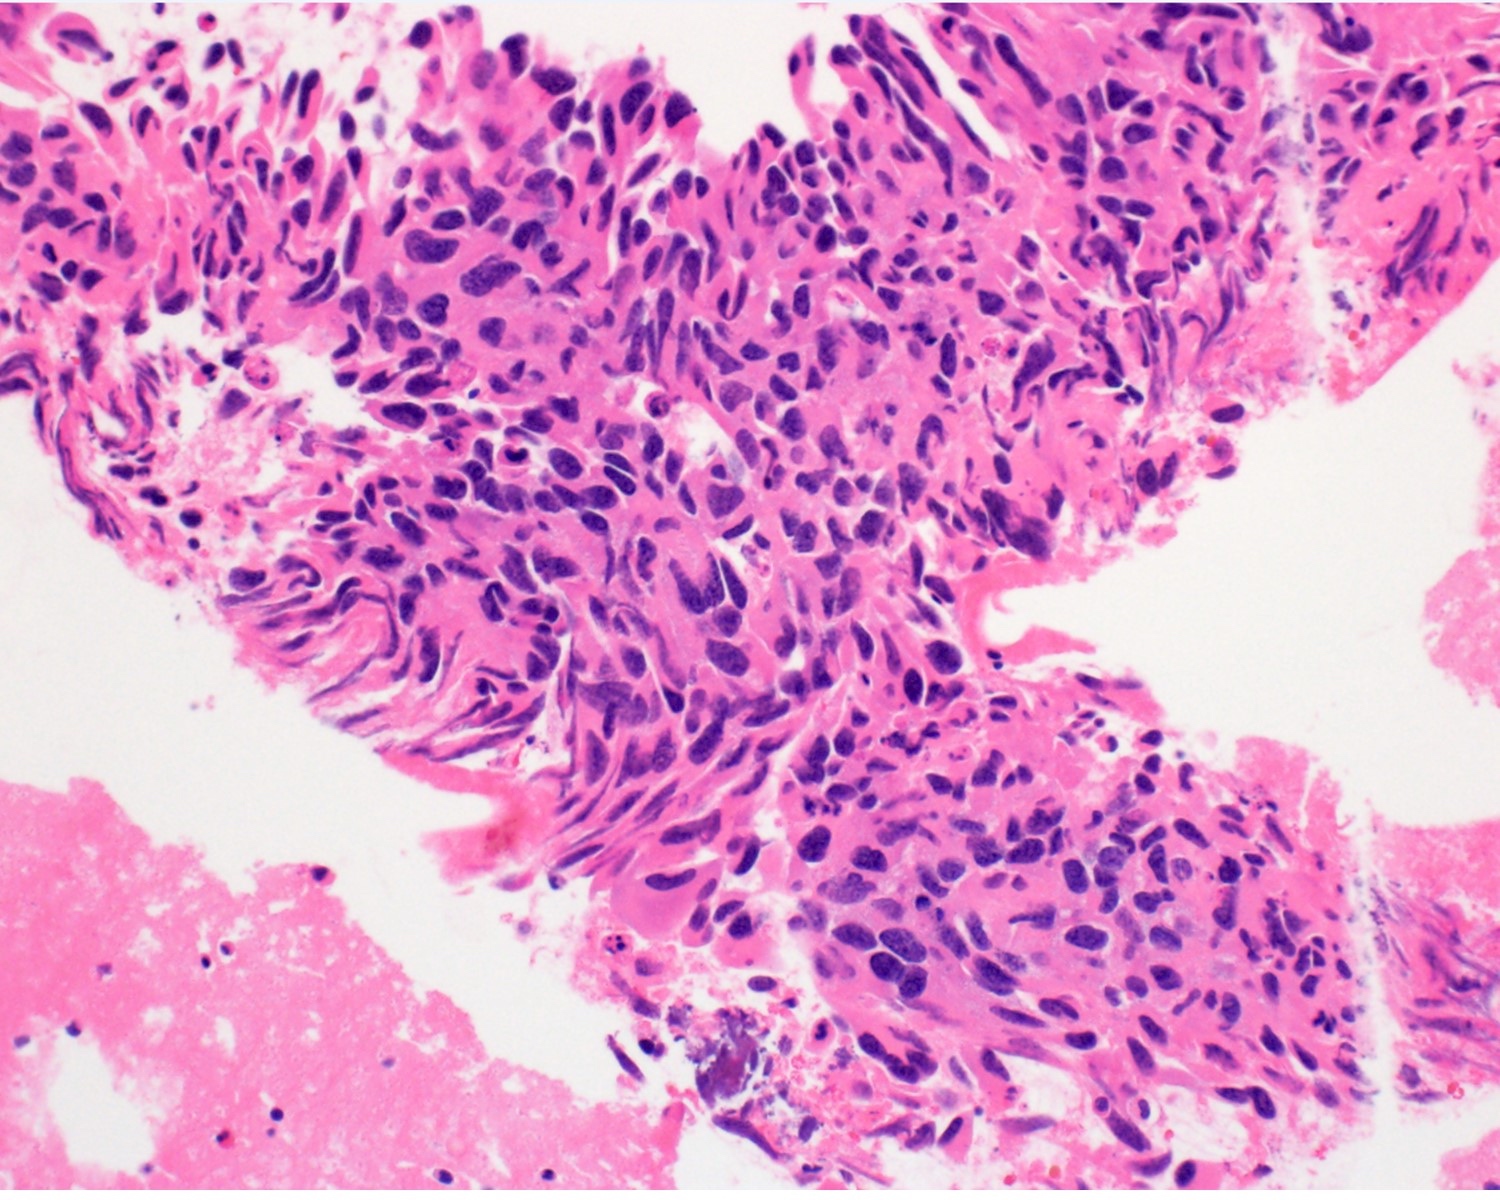

Microscopic (histologic) description

- 2 main histologic growth patterns were described (Am J Surg Pathol 2019;43:581)

- Non-mass forming

- Sinusoidal

- Dilated sinusoids lined by atypical endothelial cells seen in angiosarcoma with hyperchromatic nuclei

- Peliotic

- Blood pools and fibrin surrounded by hepatocytes

- Peripheral clusters of atypical endothelial cells seen in angiosarcoma mixed with inflammatory cells may extend into the sinusoids

- Mass forming

- Vasoformative shows architectural complexity and interconnecting vascular channels

- Anastomosing vessels and haphazard vascular channels

- Endothelial cells show tufting, atypia and mitotic figures

- Nonvasoformative shows epithelioid to spindled morphology

- Epithelioid morphology (epithelioid angiosarcoma) is most common (Am J Surg Pathol 2004;28:298)

- Solid nests or sheets of tumor cells

- Tumor often invades into sinusoids and hepatic venules at the periphery

- Cells have eosinophilic cytoplasm and oval nuclei

- Chromatin can be vesicular

- Multinucleated giant cells can be present

- Unusual growth patterns (Am J Surg Pathol 2019;43:581)

- Whorls of spindle cells in a background of chronic inflammation and loose myxoid to sclerotic stroma

- Infantile hemangioma-like angiosarcoma

- Hemangioma-like angiosarcoma

Microscopic (histologic) images